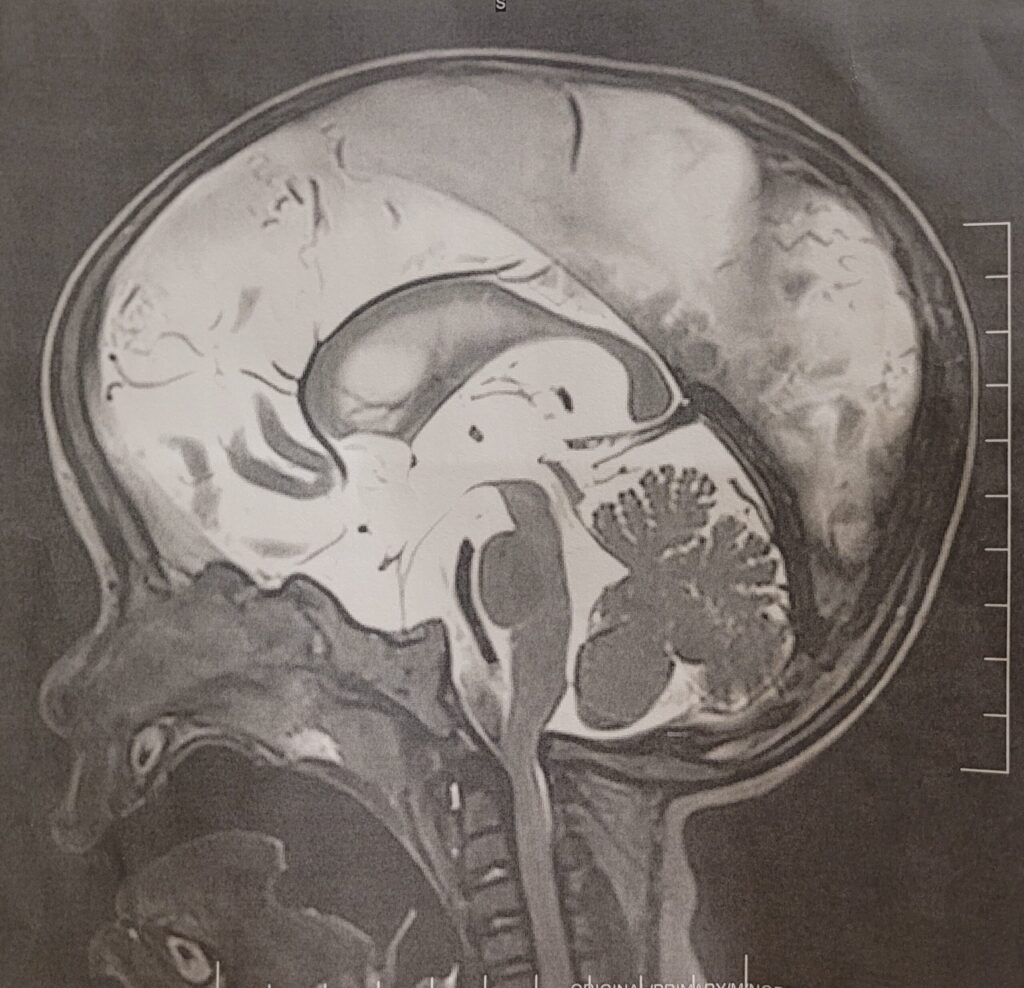

こちらが最初に撮ったMRI画像とその後全身麻酔で撮ったMRI画像です。このブレブレの画像で手術に踏み切ろうとしたなんて…今考えただけでもゾッとします…

※この時は脳神経外科手術が必要かどうかの診断をするため、頭蓋骨ずがいこつ・とうがいこつのMRI撮影をしました。

・ファーストオピニオンでのMRI撮影